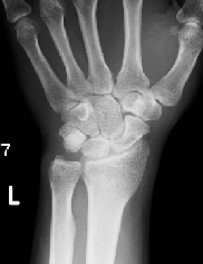

X線一般撮影

どんな検査?

放射線のひとつであるX線¹⁾を人体に照射し、各組織を通過してきたX線量の違いを画像として表示する検査です。一般撮影は放射線を利用した検査の中で最も基本となります。X線検査による被ばく²⁾は、全身被ばくではなく部分的な被ばくであり、可能な限り低い線量で検査が行われています。放射線治療など一部線量の大きい場合を除き、通常のX線検査では身体に影響を及ぼすことはありません。

何がわかるの?

体の中の骨や臓器の状態を最も手軽に画像情報として得ることができます。

■全身の骨の状態(骨折や変形がないかなど)